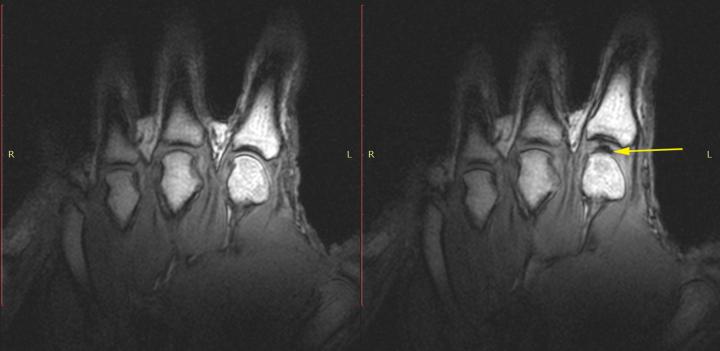

In a new study published April 15 in PLOS ONE , an international team of researchers led by the University of Alberta used MRI video to determine what happens inside finger joints to cause the distinctive popping sounds heard when cracking knuckles. For the first time, they observed that the cause is a cavity forming rapidly inside the joint.

Fryer's fingers were inserted one at a time into a tube connected to a cable that was slowly pulled until the knuckle joint cracked. MRI video captured each crack in real time--occurring in less than 310 milliseconds.

In every instance, the cracking and joint separation was associated with the rapid creation of a gas-filled cavity within the synovial fluid, a super-slippery substance that lubricates the joints.

"It's a little bit like forming a vacuum," Kawchuk said. "As the joint surfaces suddenly separate, there is no more fluid available to fill the increasing joint volume, so a cavity is created and that event is what's associated with the sound."